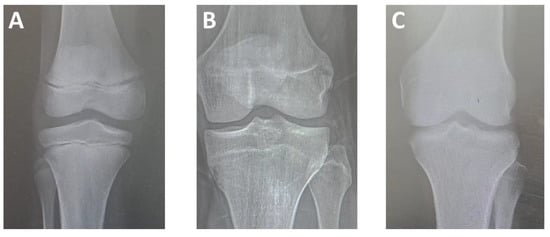

Epiphyseal union was estimated based on the three-level criteria proposed by Cameriere et al. (2012) [12], in which the classification is determined by the degree of epiphyseal ossification and the visibility of the epiphyseal scar, divided into three stages (Figure 1). The epiphyses of the femur, tibia, and fibula near the knee joint (i.e., distal end of the femur, proximal end of the tibia, and proximal end of the fibula) were evaluated from all views. Participants’ chronological age calculations were based on the date of the image and the date of birth. The observers were blinded to the age and sex of all radiographs when determining the stage of epiphyseal union for all bones, and for each stage, a score was assigned. Data from all bones (femur, tibia, and fibula) were averaged. In cases of doubt regarding the union stage, the lower stage was adopted.

Figure 1.

Plain X-ray images of the knee joint showing stages of epiphysis union; (A) Stage I, epiphysis is not fused at the distal end of the femur and the proximal ends of the fibula and tibia; (B) Stage II: epiphysis is fully ossified, and epiphyseal scar is visible at the distal end of the femur and the proximal end of the tibia; (C) Stage III, epiphysis is fully ossified, and epiphyseal scar is not visible at the distal end of the femur and the proximal end of the tibia [12].